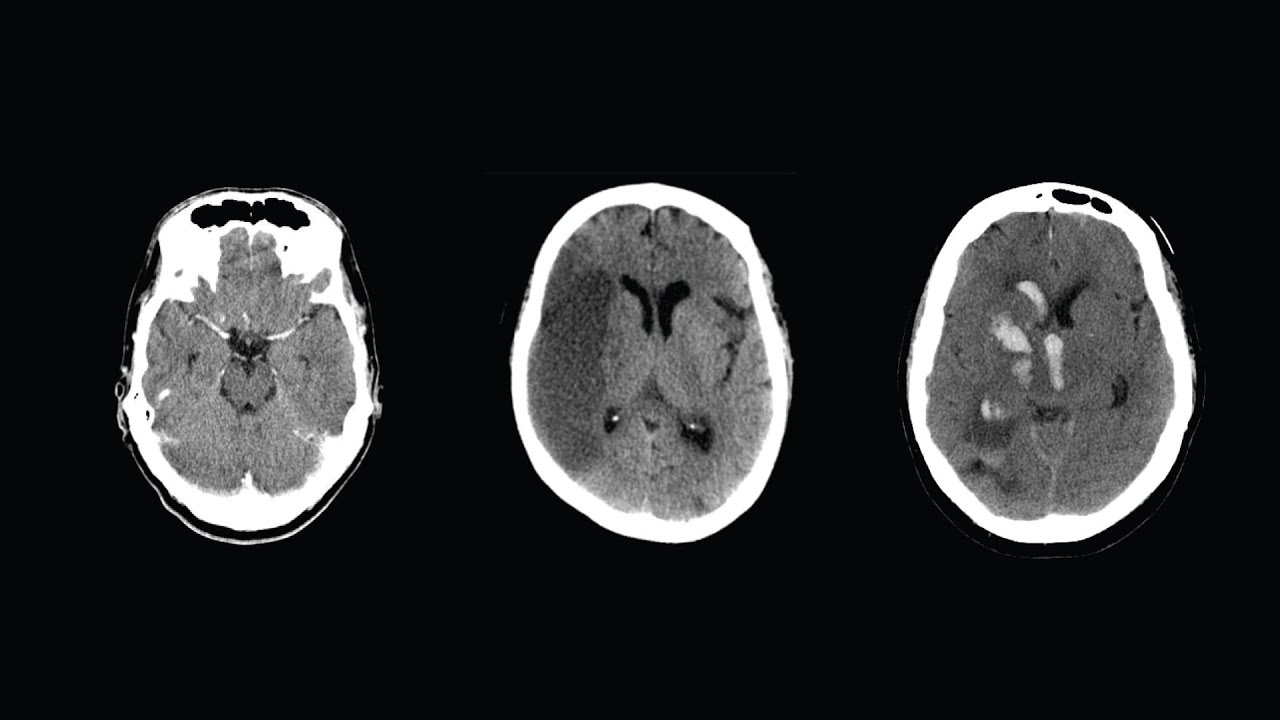

Правило, которое обязательно нужно соблюдать при оценке КТ головы: https://youtu.be/MlRsfpb40pA